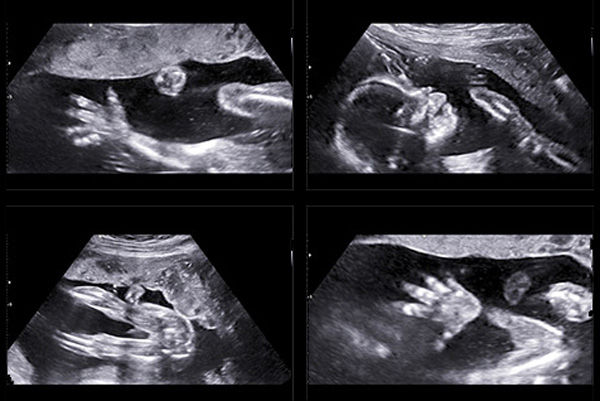

اسکن ناهنجاری در دوران بارداری

ناهنجاری در ۳ تا ۵ درصد از نوزادان در دوران بارداری مشاهده می شود. هر گونه ناتوانی یا اختلالی که از نظر فیزیکی ظاهر نوزاد را تحت تأثیر قرار دهد یا عملکرد اندام ها و سیستم های او را مختل کند، در محدوده ناهنجاری جنین است.

در حال حاضر برای پیشگیری از ناهنجاری های مادرزادی در سراسر جهان و کشور ما، هم متخصصان و هم والدین به روش های تشخیصی علمی در این زمینه اهمیت زیادی می دهند و اغلب آنها را به کار می گیرند. به طور کلی ، این روش های تشخیص ناهنجاری از تولد کودکان دارای ناتوانی جسمی و ذهنی جلوگیری می کند.

به این ترتیب والدین و فرزندان با مشکلاتی مواجه نمی شوند که در طول زندگی آنها ادامه داشته باشد. در حالی که می توان با روش های ژنتیکی در تشخیص ناهنجاری کروموزومی در دوران بارداری نتایج دقیقی به دست آورد، اما میزان تشخیص صحیح در هنگام تشخیص ناهنجاری در وضعیت فیزیکی نوزاد با استفاده از روش های بیوشیمیایی و سونوگرافی ۸۰ تا ۹۰ درصد است.